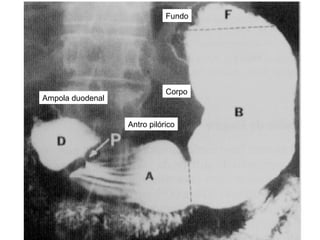

Divisão regional do estomago Cardia Localiza-se ao redor da abertura do esofago no estomago F undo gastrico A rea acima do ostio cardico; 5 º  EIE C orpo do estomago M aior regiao do estomago, intermediaria P arte pilorica P arte terminal do estomago, dividida em:  antro pilorico e canal pilorico

C orpo do estomago M aior regiao do estomago, intermediaria Cardia Localiza-se ao redor da abertura do esofago no estomago F undo gastrico A rea acima do ostio cardico; 5 º  EIE P arte pilorica P arte terminal do estomago, dividida em:  antro pilorico e canal pilorico

Fundo Corpo Antro pilórico Ampola duodenal

Fundo Corpo Antropilórico Ampola duodenal